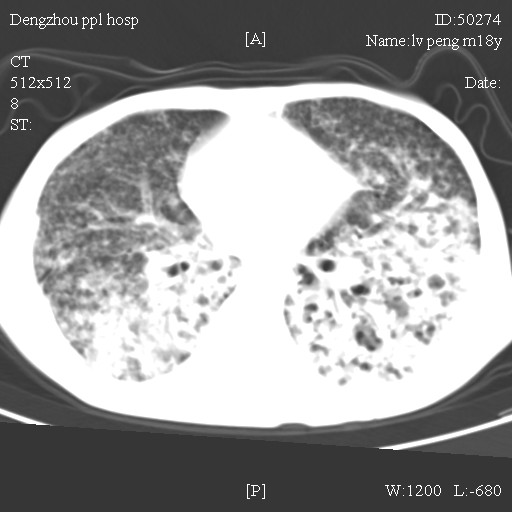

标题: CT10510:男.18岁,咳嗽咳痰两月.(有病理) [打印本页]

标题: CT10510:男.18岁,咳嗽咳痰两月.(有病理)

双肺布满大片状实变及网格状结节影,内参杂大小不等的气囊及空气支气管征,心脏增大。考虑:1 全身结缔组织疾病—系统性红斑狼仓?2 肺泡蛋白沉积症合并感染!

双肺布满大片状实变及网格状结节影,内参杂大小不等的气囊及空气支气管征,双侧胸膜腔少量积液,双下肺近膈面透亮度尚可,病人较年轻,病变较重(不知为什么上胃管?)考虑:1.胶原病肺部改变,2.组织细胞病x。结合实验室检查。

首先考虑组织细胞x病。两肺中上肺野多发囊腔,中下肺野内见多发小结节,并可见肺间质增厚。患者是男性,年龄较小。胶原性病变比较多见的类风湿、系统性红斑狼疮和硬皮病临床和影像均不是很支持,类风湿和系统性红斑狼疮的肺部表现最常见的是胸腔积液,硬皮病可见食管的扩张。

肺内多发斑片状、结节状、融合大片状及网格状影,多发薄壁空腔影,胸膜肥厚,纵隔、气管右移,考虑ⅲ型肺结核,多发空洞,继发肺间质纤维化。

双肺结核并播散.患者以肠梗阻入院,手术为肠结核.术后咳嗽做ct检查.